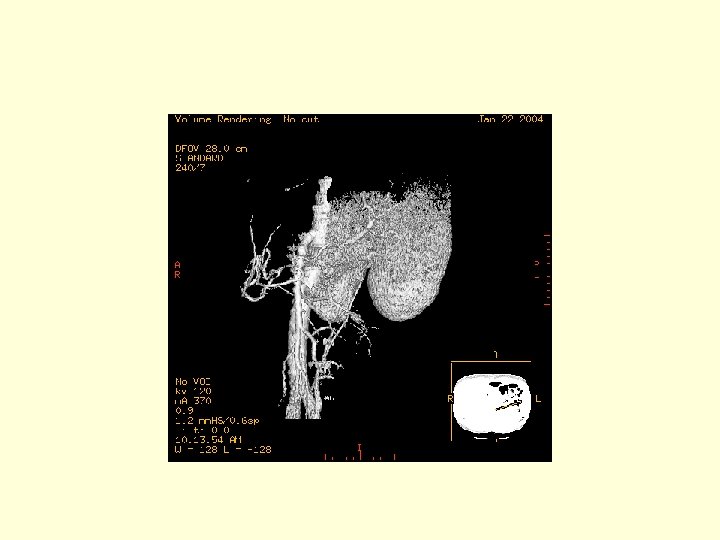

This is a 3 D image showing the branches of the SMA.

This is another 3 D image showing the vasculature of the SMA. Click through the next 20 frames to rotate the image.